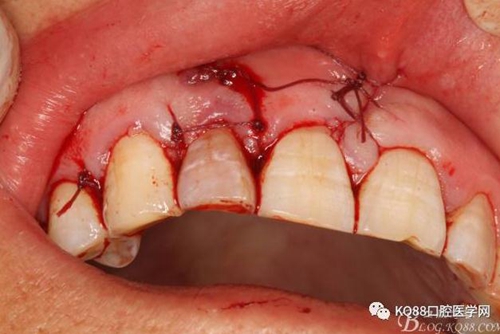

圖21.間斷縫合。

圖22.術(shù)后的x根尖片影像情況。12根尖區(qū)MTA充填完好。